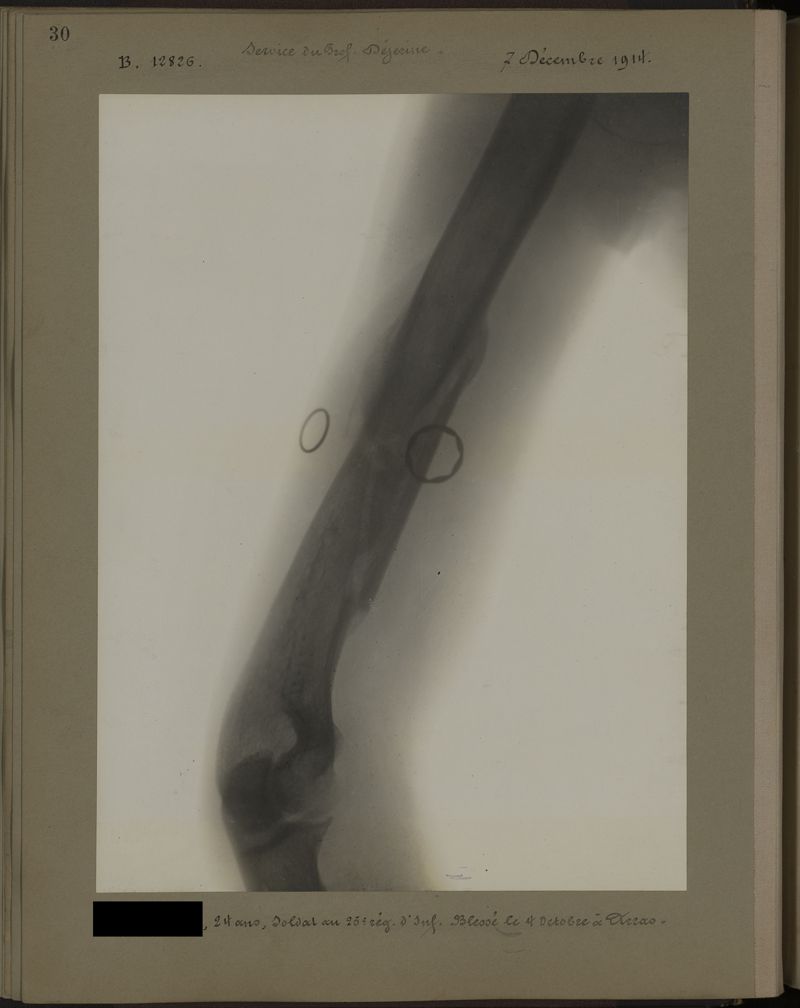

Deux albums de radiographies de la Première Guerre mondiale. Collection du laboratoire central de radiographie de la Salpêtrière. Deuxième album.

1915.